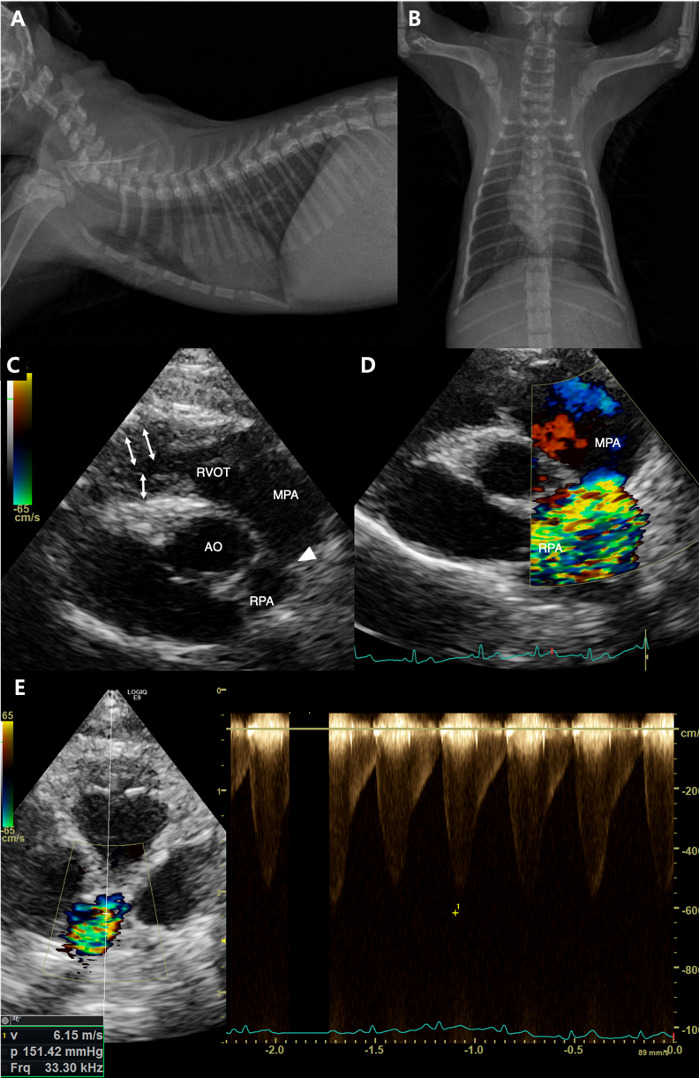

一只4个月大的英国短毛小猫被转到我们的研究所进行心脏杂音的评估。胸片和超声心动图显示右肺动脉狭窄,伴右心房扩张和右心室肥厚。通过狭窄病变的收缩血流速度为6.15 m/sec,压力梯度为151.42 mmHg。计算机断层扫描证实右肺缩窄同时伴有左肺动脉中断。行球囊血管成形术,收缩血流速度由6.15 m/sec降至2.79 m/sec,缓解右心室压力过载。一年后,胸片显示左肺萎陷和右肺恶性膨胀;然而,患者仍然无症状。在诊断后33个月,患者继续茁壮成长,没有任何临床症状。

A 4-month-old, British Shorthair kitten was referred to our institute for evaluation of a heart murmur. Thoracic radiography and echocardiography revealed narrowing of the right pulmonary artery, accompanied by right atrial dilation and right ventricular hypertrophy. The systolic flow velocity across the stenotic lesion was 6.15 m/sec, with a pressure gradient of 151.42 mmHg. Computed tomography confirmed right pulmonary coarctation with concurrent interruption of the left pulmonary artery. Balloon angioplasty was performed, reducing the systolic flow velocity from 6.15 m/sec to 2.79 m/sec and relieving right ventricular pressure overload. One year later, thoracic radiography revealed left lung collapse and right lung hyperinflation; however, the patient remained asymptomatic. At 33 months post-diagnosis, the patient continued to thrive without any clinical signs.